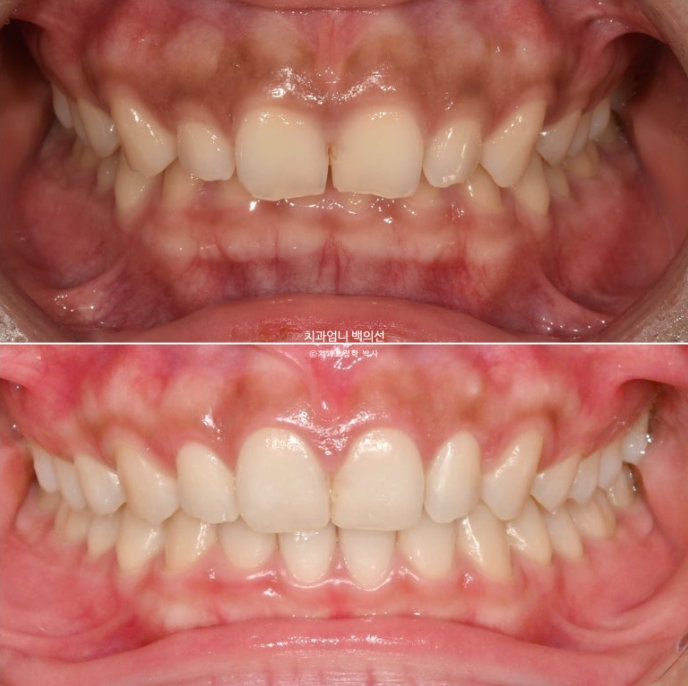

오늘은 앞니가 깊게 물리는 과개교합과 거미스마일이 있을 때 인비절라인 라이트로 단기간에 어떤 것을 할 수 있는 지 보여드리겠습니다.

24년 3월 잇몸성형을 위해 오신 분입니다.

위 앞니 4개가 전반적으로 짧은 편이고 웃을 때 잇몸이 많이 보이는 거미스마일이 있습니다.

잇몸성형으로 거미스마일을 어느정도는 해결할 수 있지만 앞니가 뒤로 쓰러진 옥니이고 깊게 물리는 과개교합도 있고 앞니 사이도 벌어져 있어서 교정을 권유드렸습니다.

어금니교합은 좋습니다.

위 앞니가 아래 앞니를 깊게 덮어 아래앞니가 전혀 보이지 않는 정도의 심한 과개교합입니다.

위 앞니는 정상각도보다 뒤로 쓰러진 옥니입니다

앞니 사이사이에 벌어진 틈도 있습니다.

24.03~25.01

좋아진 배열과 사라진 틈.

과개교합의 확실한 개선